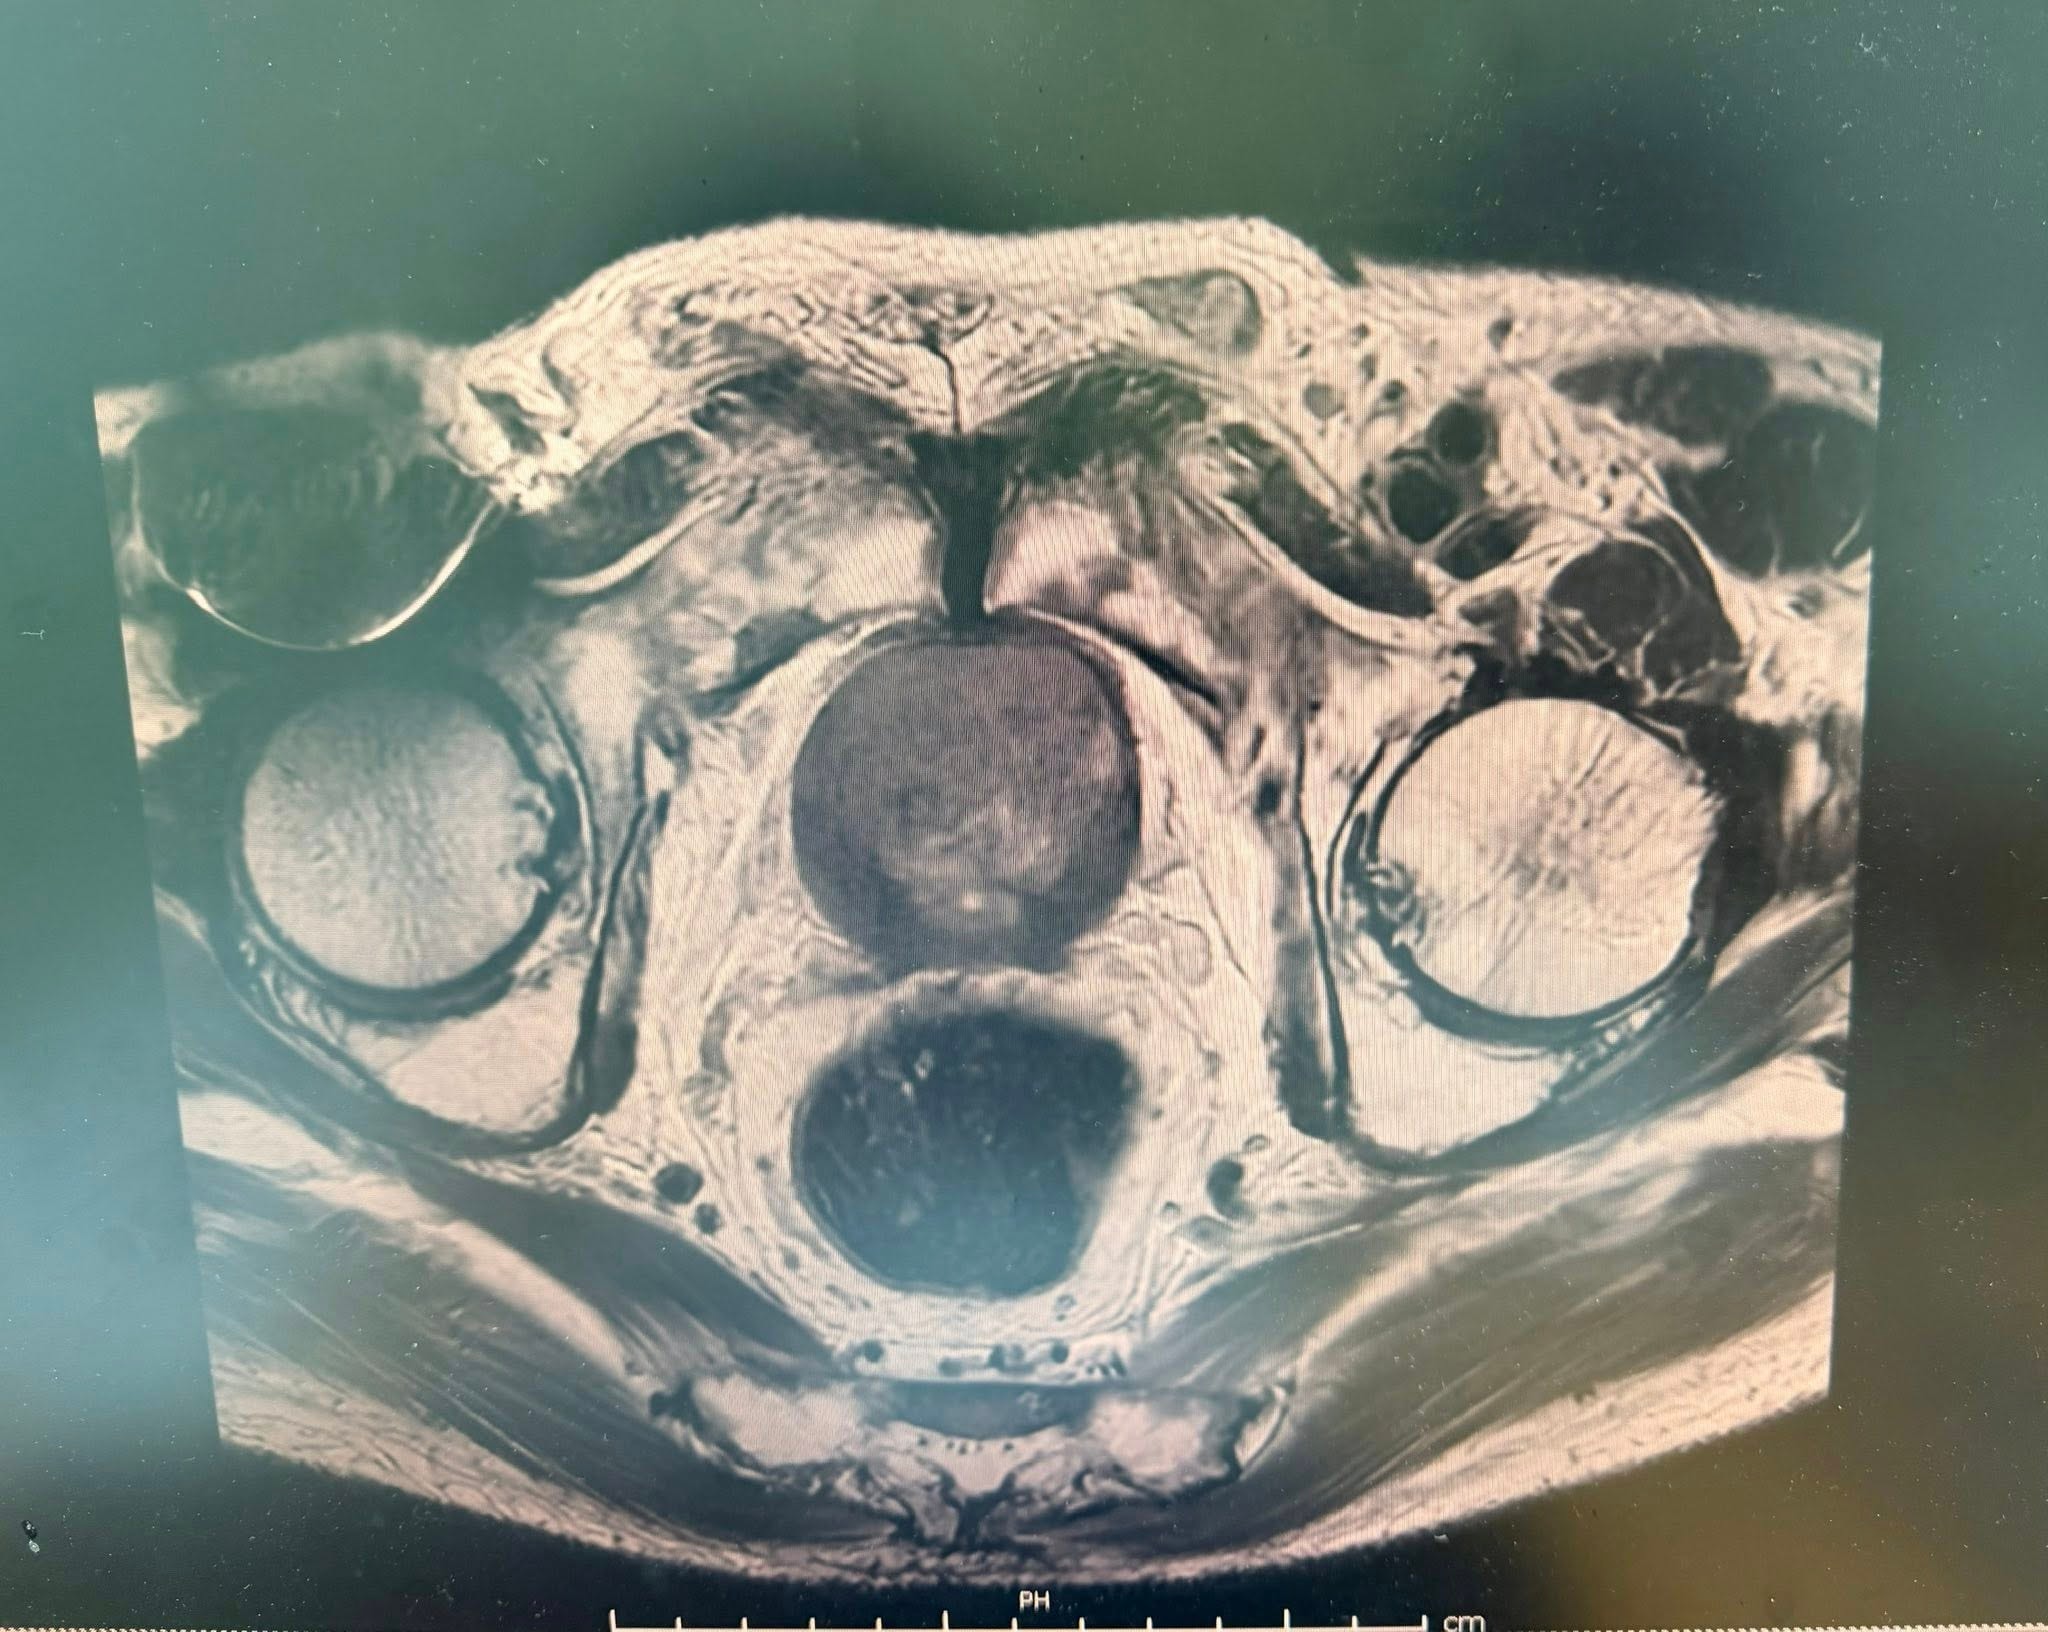

Chụp cộng hưởng từ đa tham số (mpMRI) xác định tuyến tiền liệt kích thước khoảng 49×46×37mm (thể tích ~43cm³). Tổn thương vùng ngoại vi phía sau lệch trái kích thước 9×12mm, bờ không đều, xâm lấn túi tinh cùng bên, được phân loại PIRADS 5 – mức độ nghi ngờ ung thư rất cao.

Ngoài ra, hình ảnh còn ghi nhận các nốt bất thường tại xương chậu hai bên và xương cùng, gợi ý khả năng di căn xương. Đồng thời phát hiện thoát vị bẹn trái kích thước khoảng 25×15mm.

Các bác sĩ nhận định, chụp cộng hưởng từ đóng vai trò then chốt trong việc khoanh vùng chính xác tổn thương nghi ngờ để định hướng sinh thiết.

Hình ảnh chụp khối u tiền liệt tuyến của bệnh nhân. Ảnh: